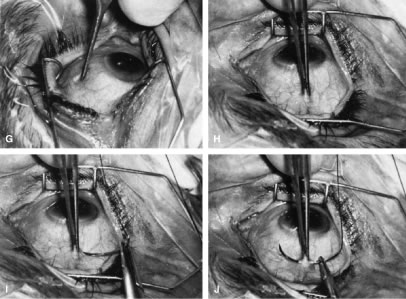

irrigated away, and chamber deepening cannot readily be performed.  Fig. 10. Peripheral iridectomy with the use of a preplaced suture to retract the

edges of the incision. A. An incision is made through two thirds of the thickness of the sclera

directly at the corneoscleral sulcus. B. A 9-0 white virgin silk suture is placed so that it will be able to be

retracted from the depths of the incision. C. The suture is looped and used to retract the edges of the incision superiorly

and inferiorly. The incision is completed, permitting prolapse

of a small knuckle of iris. D. The iris is grasped with a fine-toothed forceps. E. The iris is pulled over the blade of the DeWecker scissors; after the

position of the iris is noted, the blades are closed and the tissue is

excised. F. The tip of an irrigator is placed just inside the incision, with care

taken to ensure that it does not enter the anterior chamber. Remnants

of the pigment epithelium are flushed away, and the iris is permitted

to return to its proper position so that the pupil is completely round. (Spaeth GL. Glaucoma surgery. In Spaeth GL (ed). Ophthalmic Surgery: Principles

and Practice. Philadelphia: WB Saunders, 1990.) Fig. 10. Peripheral iridectomy with the use of a preplaced suture to retract the

edges of the incision. A. An incision is made through two thirds of the thickness of the sclera

directly at the corneoscleral sulcus. B. A 9-0 white virgin silk suture is placed so that it will be able to be

retracted from the depths of the incision. C. The suture is looped and used to retract the edges of the incision superiorly

and inferiorly. The incision is completed, permitting prolapse

of a small knuckle of iris. D. The iris is grasped with a fine-toothed forceps. E. The iris is pulled over the blade of the DeWecker scissors; after the

position of the iris is noted, the blades are closed and the tissue is

excised. F. The tip of an irrigator is placed just inside the incision, with care

taken to ensure that it does not enter the anterior chamber. Remnants

of the pigment epithelium are flushed away, and the iris is permitted

to return to its proper position so that the pupil is completely round. (Spaeth GL. Glaucoma surgery. In Spaeth GL (ed). Ophthalmic Surgery: Principles

and Practice. Philadelphia: WB Saunders, 1990.)